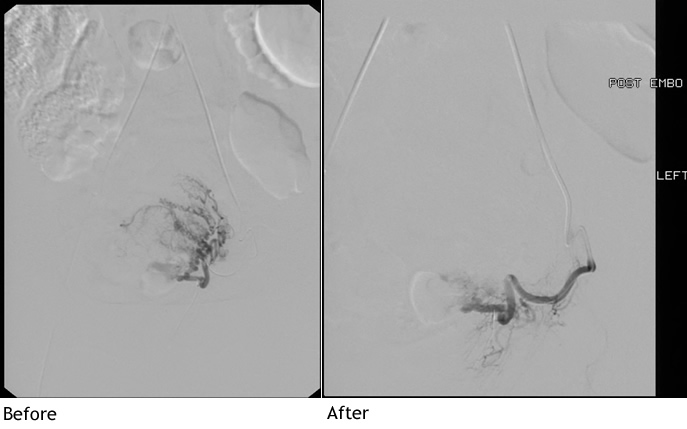

UFE is a minimally invasive technique used to treat symptomatic uterine fibroids. The patient lies on her back on a specialized procedure table. Intravenous sedative medications and local anesthetic agents are given to assure patient comfort. A small plastic tube (catheter) is placed into the blood vessel in the groin. A fluoroscopy (x-ray) camera is used to guide the catheter into the uterine arteries where tiny particles are injected to block the blood supply to the fibroid tumors. Patients typically stay in the hospital for one to two days following the procedure.

UFE is performed when fibroid tumors produce undesirable symptoms. Fibroids are common benign tumors of the wall of the uterus that are often asymptomatic but can produce heavy menstrual bleeding or severe pelvic pain. Potential candidates are evaluated prior to the procedure by one of our interventional radiologists; Patients also require evaluation by a gynecologist, laboratory studies, and an ultrasound or MRI examination of the pelvis prior to the procedure.